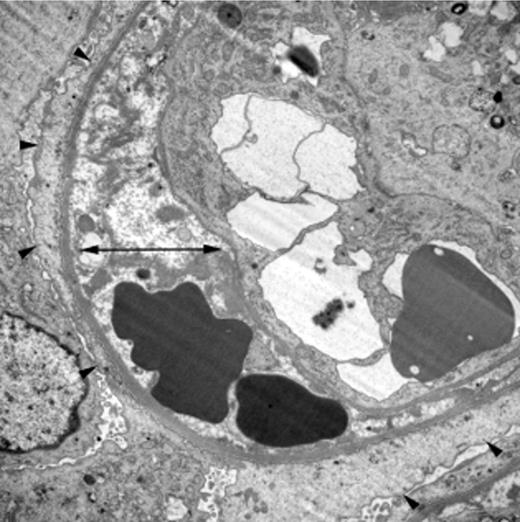

TA-TMA is a pathologic diagnosis, with renal findings involving the glomerular capillaries and other vessels. The histologic features of TA-TMA in the kidney include thickened capillary walls, fragmented erythrocytes, occluded vascular lumens, and endothelial separation with swelling, fibrin deposition, and necrosis (Figure 1).3,5 Similar pathologic features are also found in TTP, aHUS, and diarrhea-positive HUS, although thrombi may contain relatively different proportions of platelets and fibrin according to diagnosis.5,44 Furthermore, patients with TA-TMA have rarely been reported to have systemic thromboses, in contrast to patients with TTP.3,7

Characteristic renal histology in TA-TMA. Electron microscopy (×8000) from the kidney biopsy of a child who developed TA-TMA after autologous HSCT. It shows irregular electron-lucent expansion of the subendothelial zone (double arrow) and diffuse podocyte foot process fusion, a sign of damage to the glomerular filtration barrier (arrowheads). Reprinted by permission from Macmillan Publishers Ltd.13